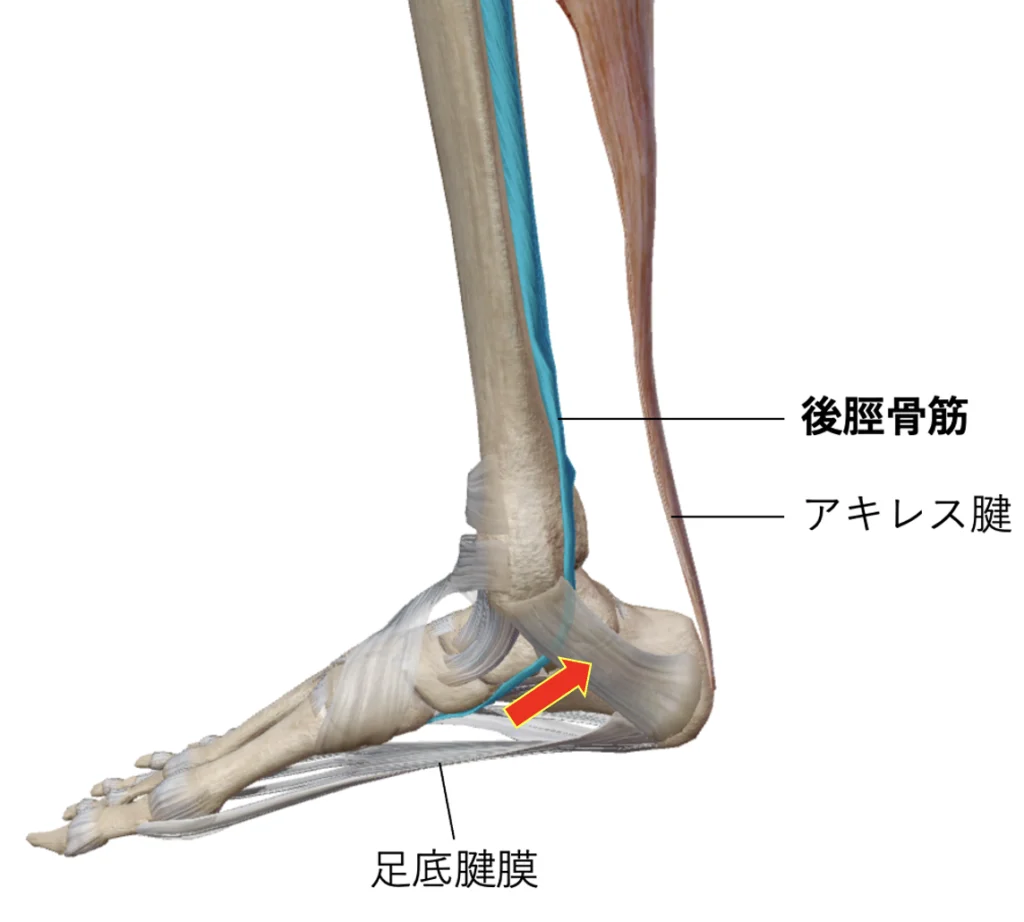

原因と病態後脛骨筋による外脛骨部への牽引作用

外脛骨は足部過剰骨の中で最も頻度が高く、後脛骨筋腱がくっついている舟状骨の内側後方にみられます。女性に多く80〜90%は両側性です。

②扁平足を合併し、後脛骨筋の筋力低下による後足部のoverpronation(踵周辺の関節が過剰に動きすぎている状態)に伴って生じる外脛骨周囲全体の痛み

③慢性的な後脛骨筋腱炎

④外傷をきっかけに後脛骨筋腱を介して生じた牽引力、剪断力、圧迫力などによって線維軟骨結合が損傷されて生じた痛み